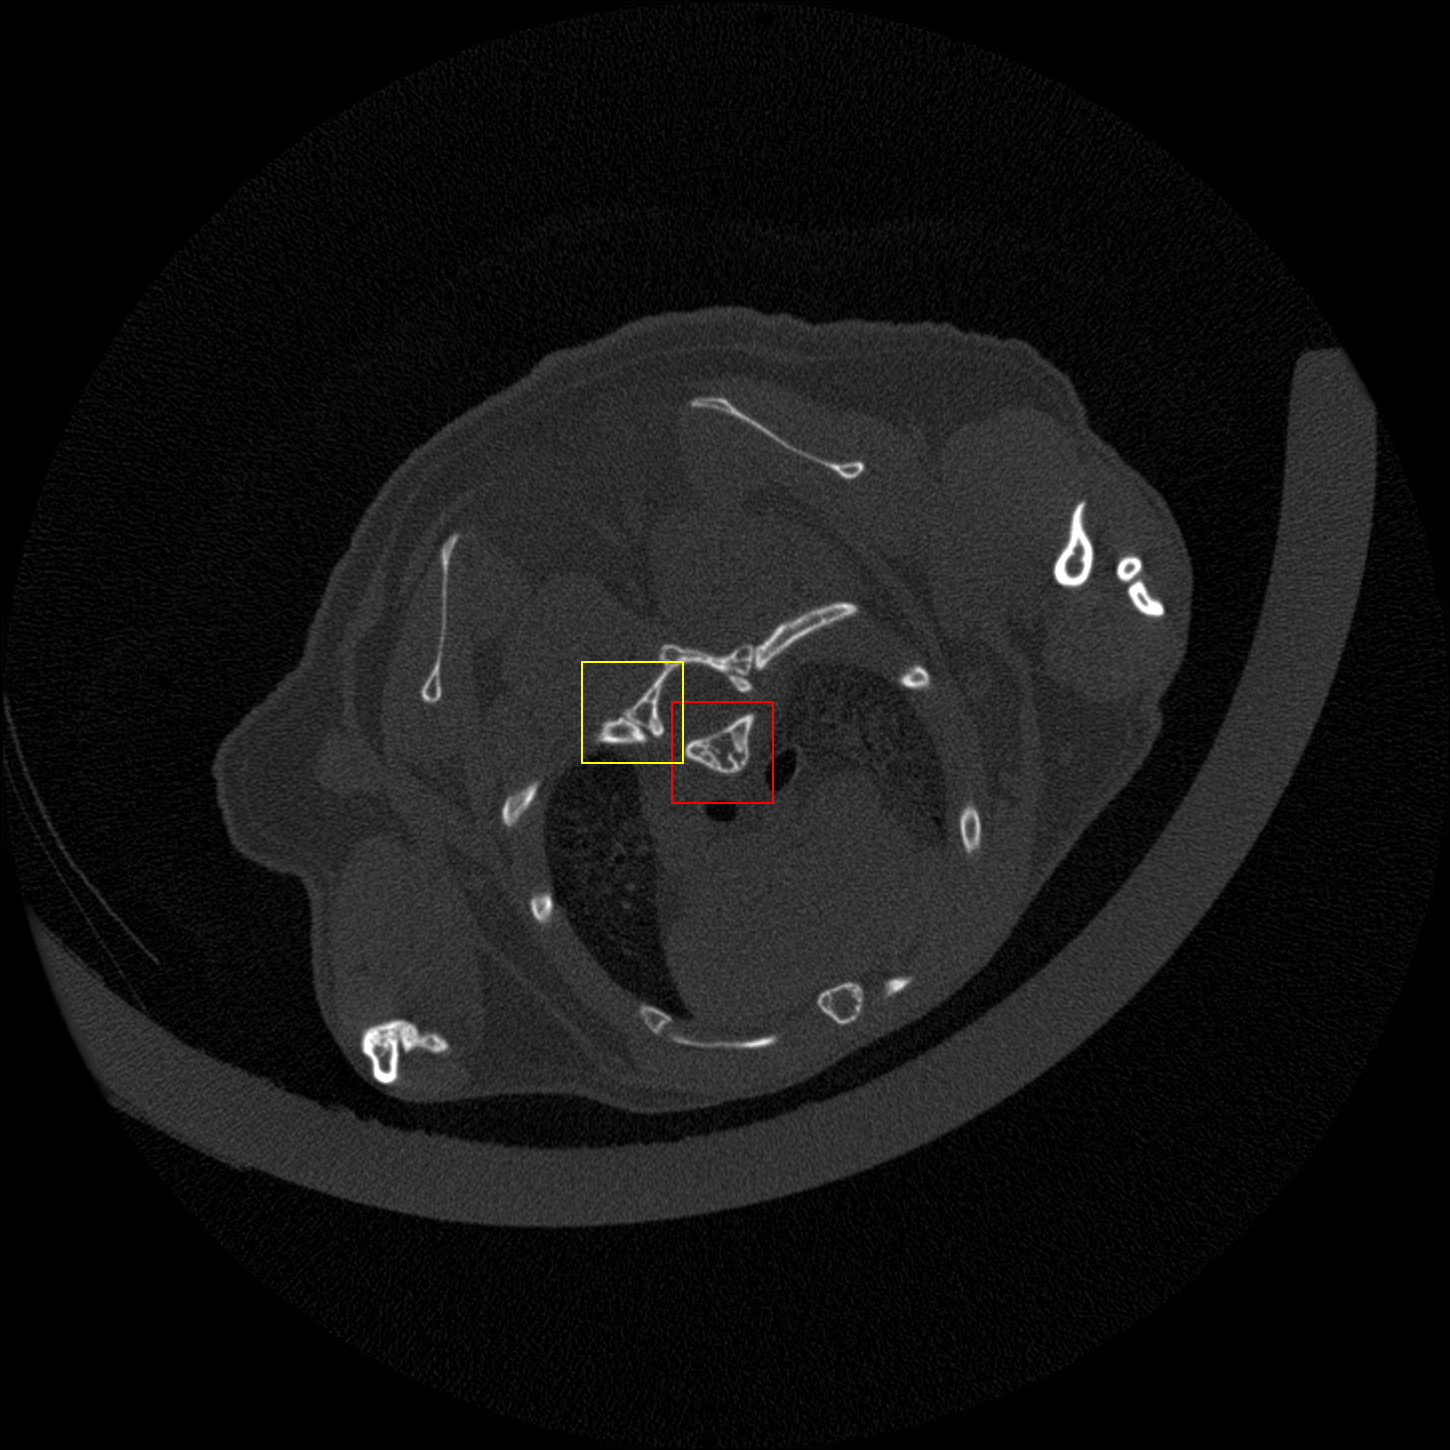

Figure 4: Visual comparsion of SRCT Case 111 from the Tibia dataset. The restored bony structures are shown in the red and yellow boxes in Fig. 5. The display window is [-900, 2000] HU.

Figure 5: Zoomed regions of interest (ROIs) marked by the red rectangle in Fig. 4. The restored image with GAN-CIRCLE reveals subtle structures better than the other variations of the proposed neural network, especially in the marked regions. The display window is [-900, 2000] HU.

III-D Experimental Results with the Tibia Dataset